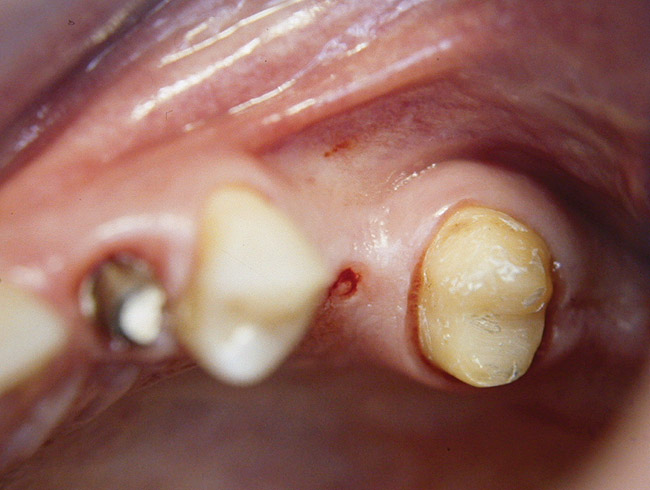

At the time of surgery, the tooth was extracted without harvesting any mucosal flap because the implant site was prepared by means of a pilot drill bur (Figure 13) and alternating osteotomes (Figure 14A and Figure 14B). The implant was positioned and showed primary stability. The implant was loaded 2 days after surgery. Then, splinted PFM crowns supported by custom gold abutments were delivered. At 6 months posttreatment, the radiograph revealed no bone resorption and the clinical result was optimal (Figure 15A and Figure 15B).

Figure 15 A Final implant-supported PFM restorations.

Figure 15B Posttreatment radiograph, 6 months after the initial surgery.

Figure 15a  Final implant-supported PFM restorations.

Figure 15a

Figure 15  Posttreatment radiograph, 6 months after the initial surgery.

Figure 15b